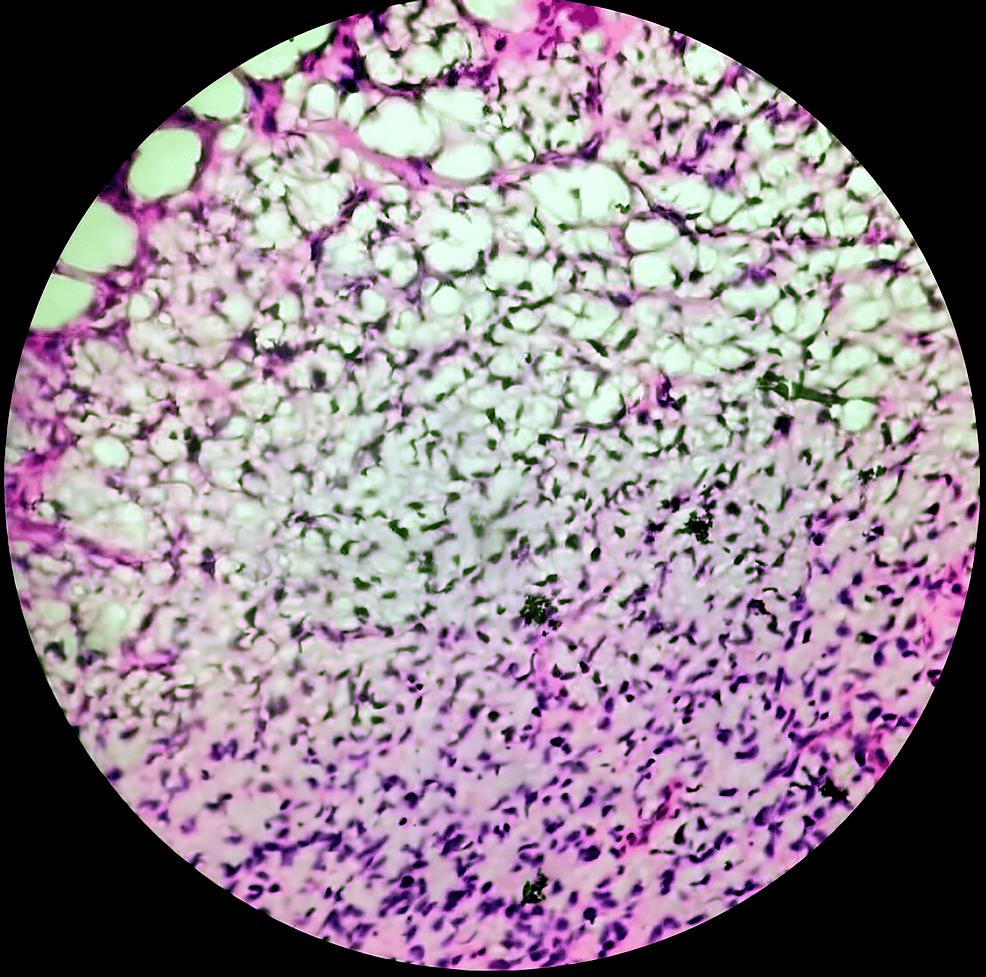

Undifferentiated spindle cell HE stained section; 200× Spindle Cell Sarcoma Grade 2 spindle cell sarcoma is a type of undifferentiated sarcoma. Spindle cell sarcoma is a rare form of bone cancer or soft tissue cancer. a score of 1 means cancer cells look similar to normal cells. They tend to grow and spread quickly. It can occur anywhere throughout the body, but it most. soft tissue sarcomas (sts) are. Spindle Cell Sarcoma Grade 2.